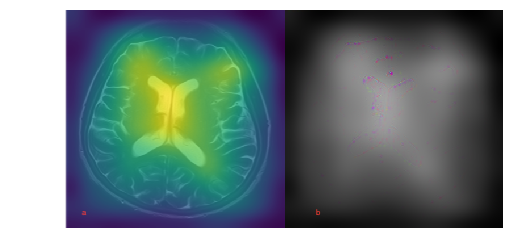

In addition to model quality, the model interpretability is significant. We, therefore, investigate, which specific part of the image is most important for the model learning. We use the Gradient-weighted Class Activation Mapping (Grad-CAM) method to this end [26]. In general, this method uses the activation maps of the last convolution layer to visualize the areas responsible for the decision making about the class prediction and weighs them with the help of the predicted class gradients.

Furthermore, we used Grad-CAM method for the model result interpretation in our work. Figure 1 is demonstrating that the most important information used by the model is contained in the images of the brain liquor system.

Figure 1: Deep neural network interpretation with (a) activations maps on the left, and (b) Grad-CAM on the right.